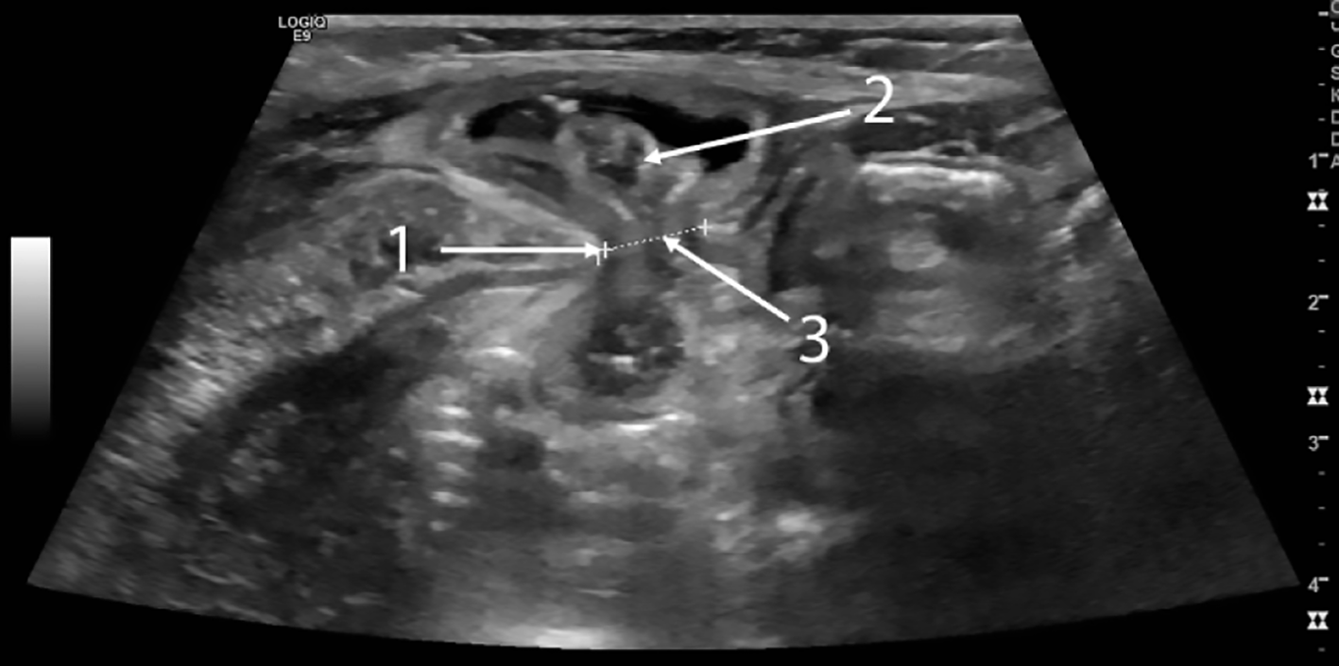

Figure 4 Ultrasound image of hernia protrusion at the time of strangulation.

1: Muscle edge; 2: Loop of intestine; 3: Hernia gates.